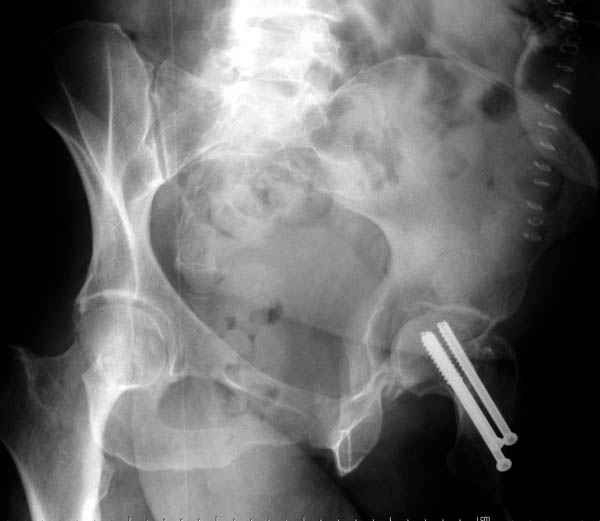

Из-за упущенного времени (три недели с момента

поступления) ацетабулум ведем консервативно.

На снимке ацетабулума редко встречающийся очень низкий перелом, наверное, трудно было репозицию через один доступ? Перелом как бы замкнулся в квадрилатеральной поврехности.